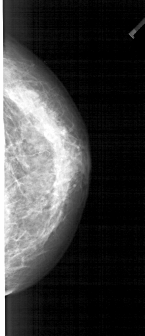

A_1938_1.RIGHT_CC

RIGHT_MLO LINES 4711 PIXELS_PER_LINE 2326 BITS_PER_PIXEL 12 RESOLUTION 43.5 NON_OVERLAY